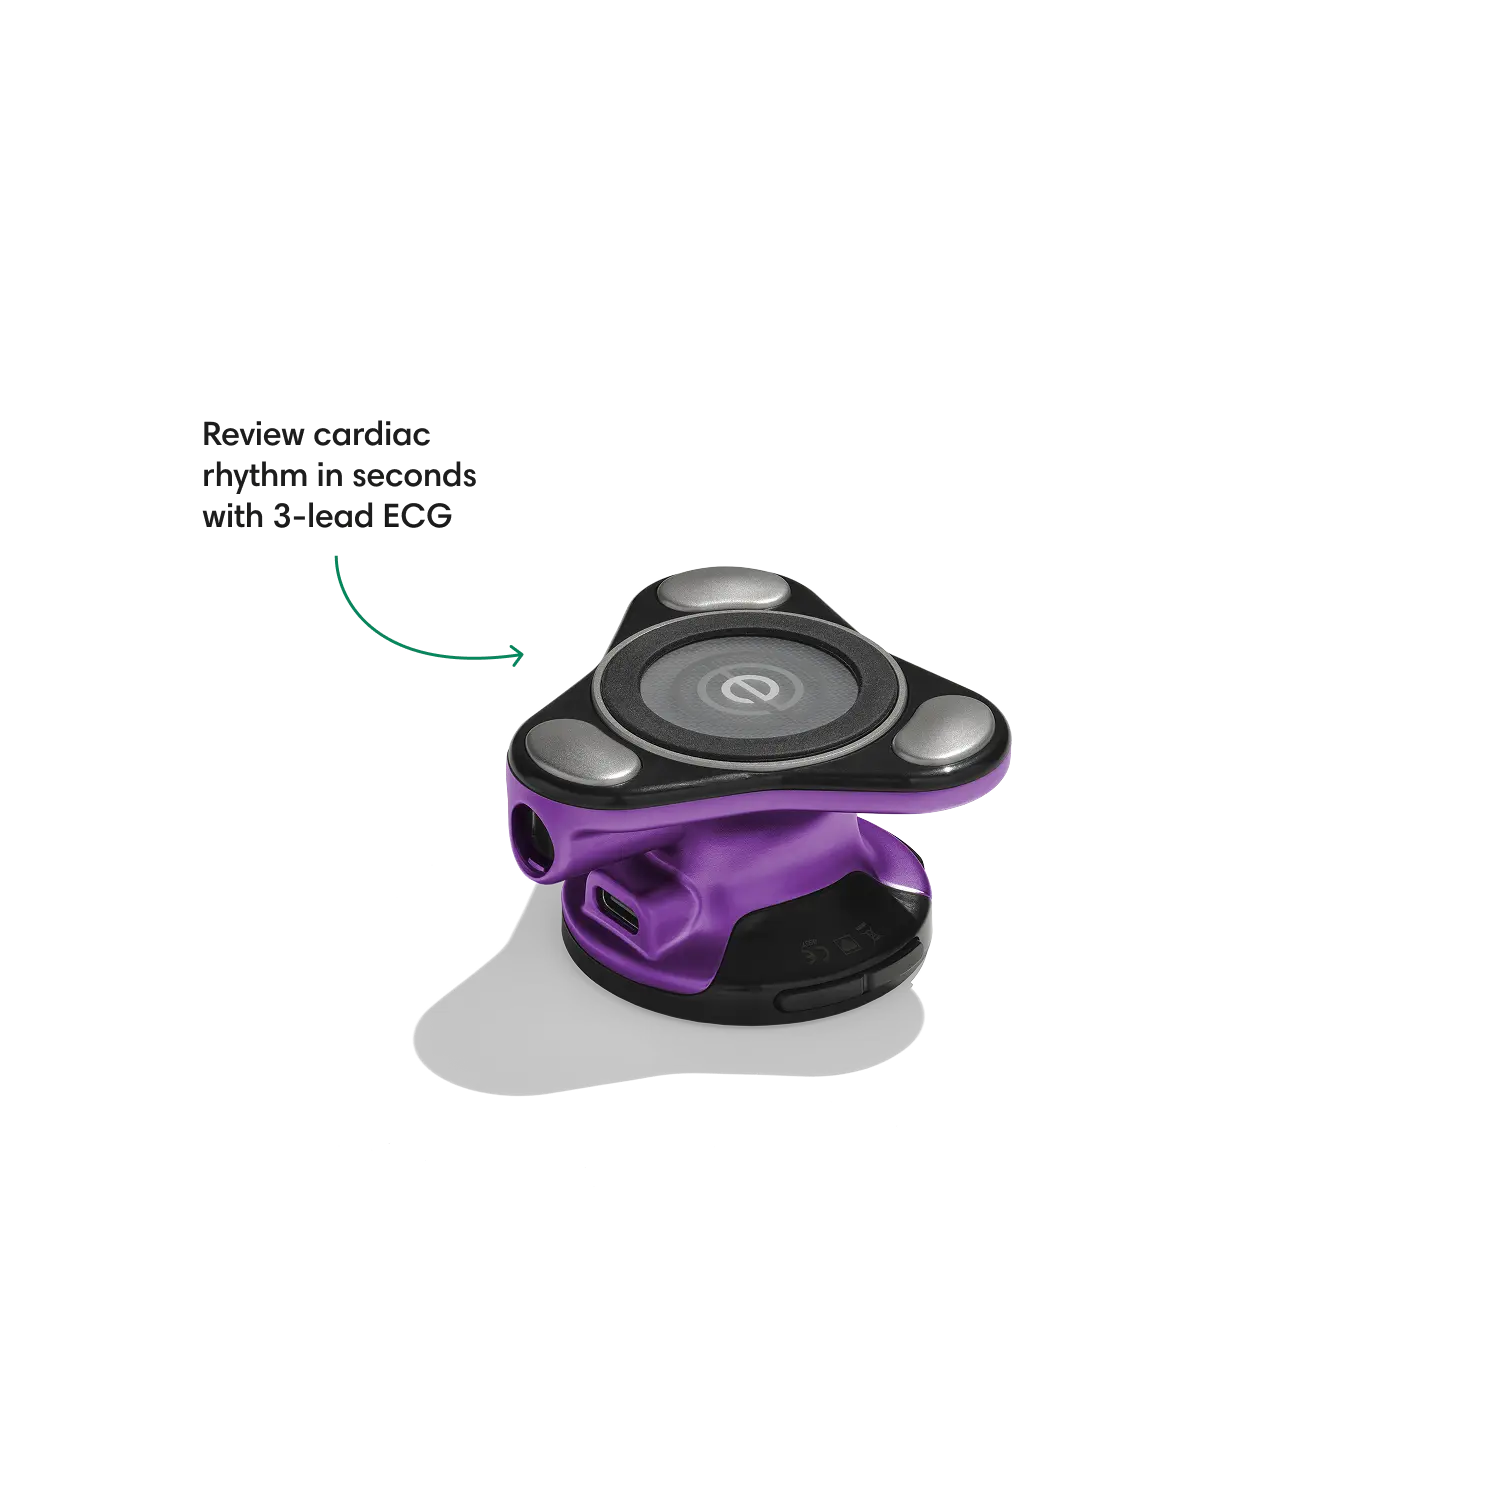

Go beyond sound alone.

For the first time ever, measure heart rate, visualize 3-lead ECG, and see detection results — right on a built-in, full-color display.